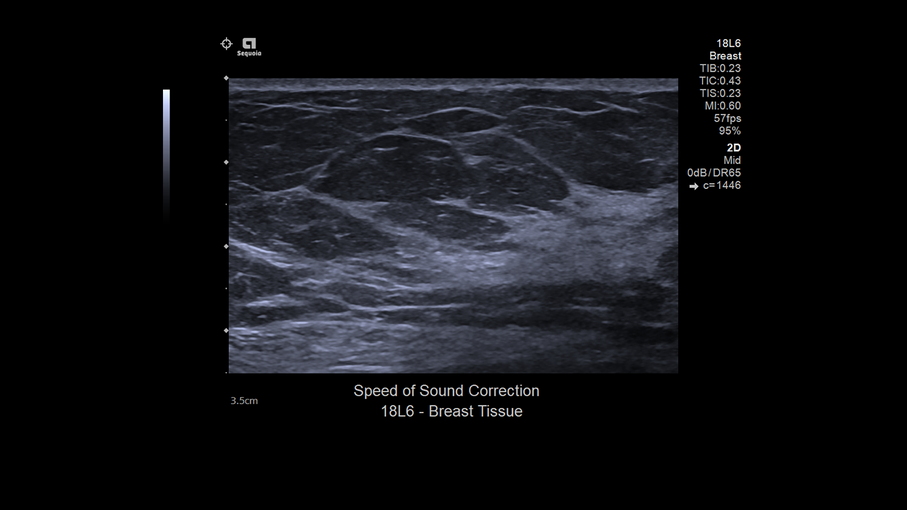

Кроме новой техники, можно заказать восстановленные медицинские системы: ультразвуковые сканеры, томографы, флюороскопы, ангиографы и хирургические установки С-дуга.